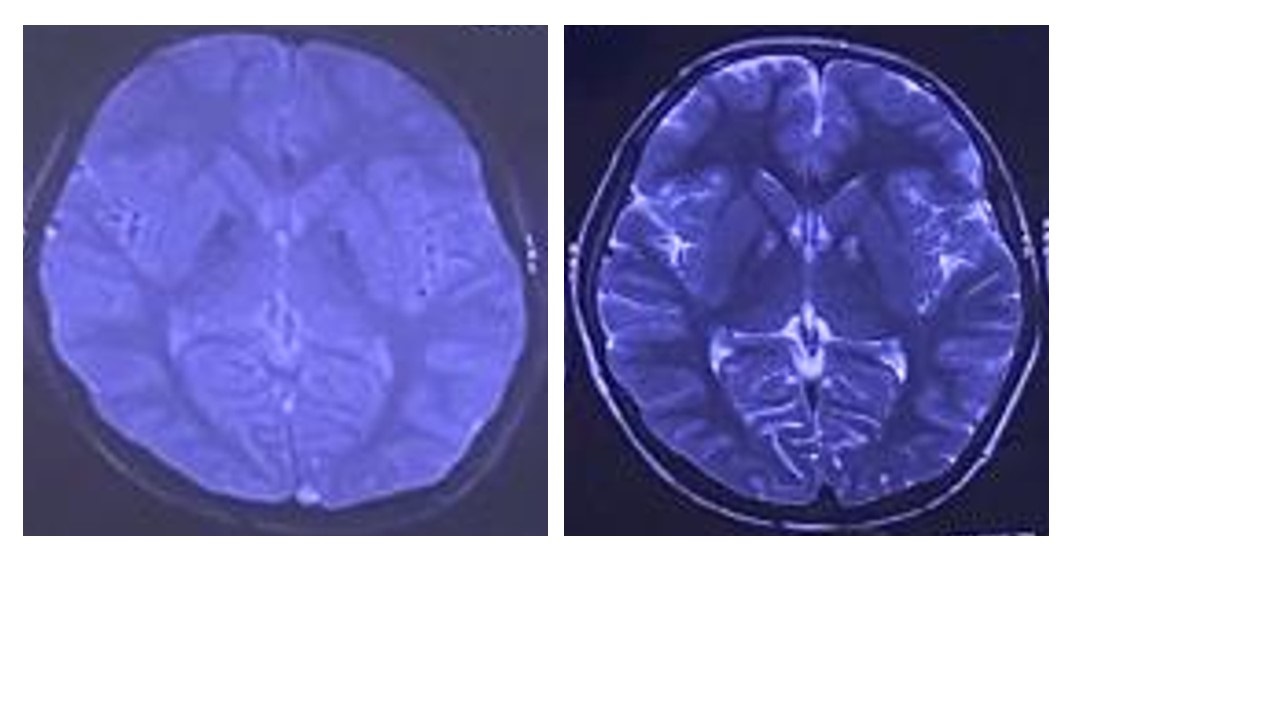

Results: Routine investigations and slit lamp examination were normal. His T2WMRI showed ‘eye -of- the- tiger’ sign (Fig2) and iron accumulation in SWI. Typical PKAN was suspected because of the rapidly progressive generalized dystonia and the typical radiological sign. So, genetic testing for PANK2 mutation was pursued.

Eye-of-the-tiger sign on T2WI;hypointensity on SWI